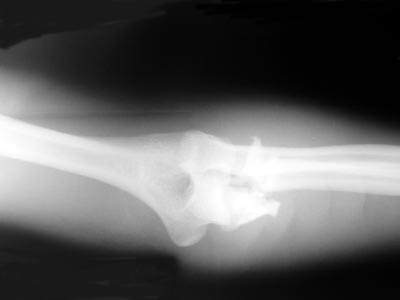

AC is a 25 year old male who was assaulted with a baseball bat. He sustained a shattered proximal ulna fracture with elbow dislocation. Surgery required application of a plate and screws, as well as pinning and cerclage wiring. He worked diligently in therapy to regain the excellent range of motion in his elbow as demonstrated in the photo with me.